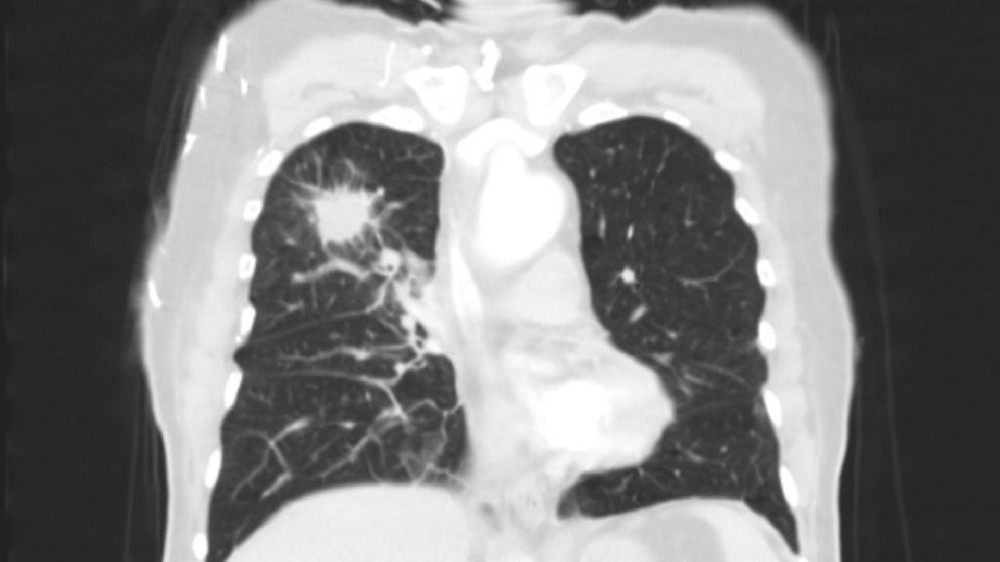

美國代謝腫瘤研究所(AICM)由李國華博士創立的世界級醫療機構,以諾貝爾獎得主Otto Warburg的 "癌細胞能量代謝學說" 爲基石,首創顛覆性 "四位一體靶向代謝療法":通過代謝重編程斬斷腫瘤能量鏈+ 節拍控瘤封鎖轉移路徑 + 基因靶向清除突變根源 + 免疫調節構築終身防禦,徹底改寫癌症治療規則!該療法已登陸美國希望之城、MD安德森癌症中心、凱特琳癌症中心等全球頂級機構,並依託香港代謝腫瘤中心及前海泰康醫院建立亞洲核心基地,專爲中晚期/難治性癌症患者提供趨近零副作用的創新性治療,實現癌痛癌疲乏突破性緩解及生存週期的治癒級延長,讓複雜病例重獲生命掌控權!